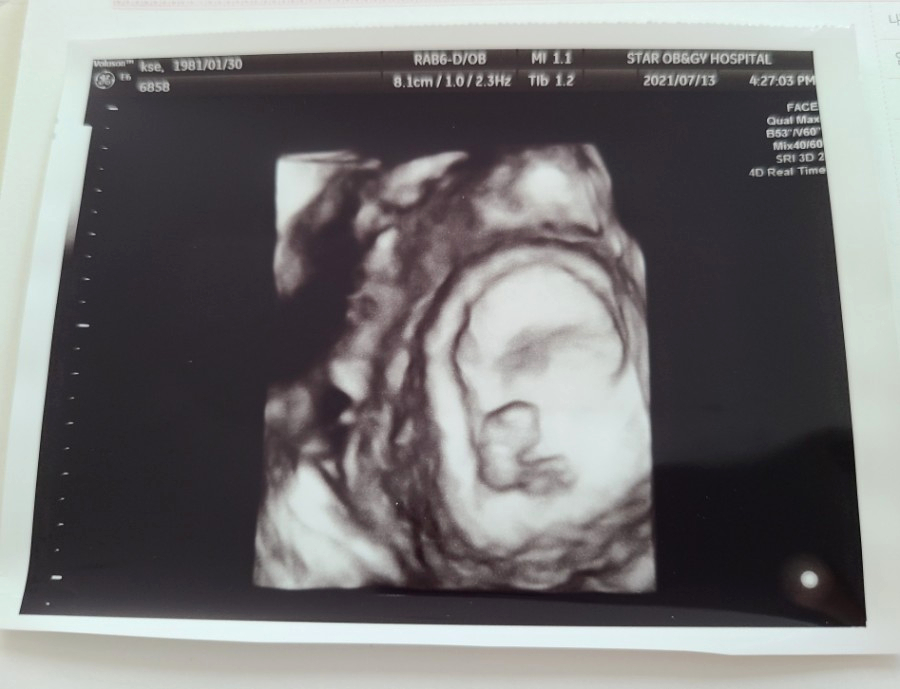

아무튼 7월 13일을 기준으로 전 8주 차가 되었다고 하셨고 이날 처음으로 아기의 심장박동을 확인할 수 있었어요.

아기의 크기는 1.67CM. 이날 아기의 얼굴과 몸도 초음파로 볼 수 있었어요.